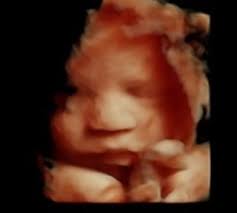

Sweet baby face louisville ky. March 1 2020. Sweet Baby Face is a 3D 4D Ultrasound and Baby Boutique in Louisville Elizabethtown KY. See your child in more depth and detail.

Pregnancy and Childbirth Service Near Sweet Baby Face. They give you a much clearer view of your child than the traditional 2D ultrasound you may even see if your baby has you or your partners features. Company Profile Contact information Current and former Employee directory Corporate history statetax IDs.

We do 2D 3D 4D HD5D elective ultrasound images in Louisville Elizabethtown. Millions of Products Top Brands. Combining cutting-edge technology with a spa theater environment we bring unbelievable images of your unborn baby to life.